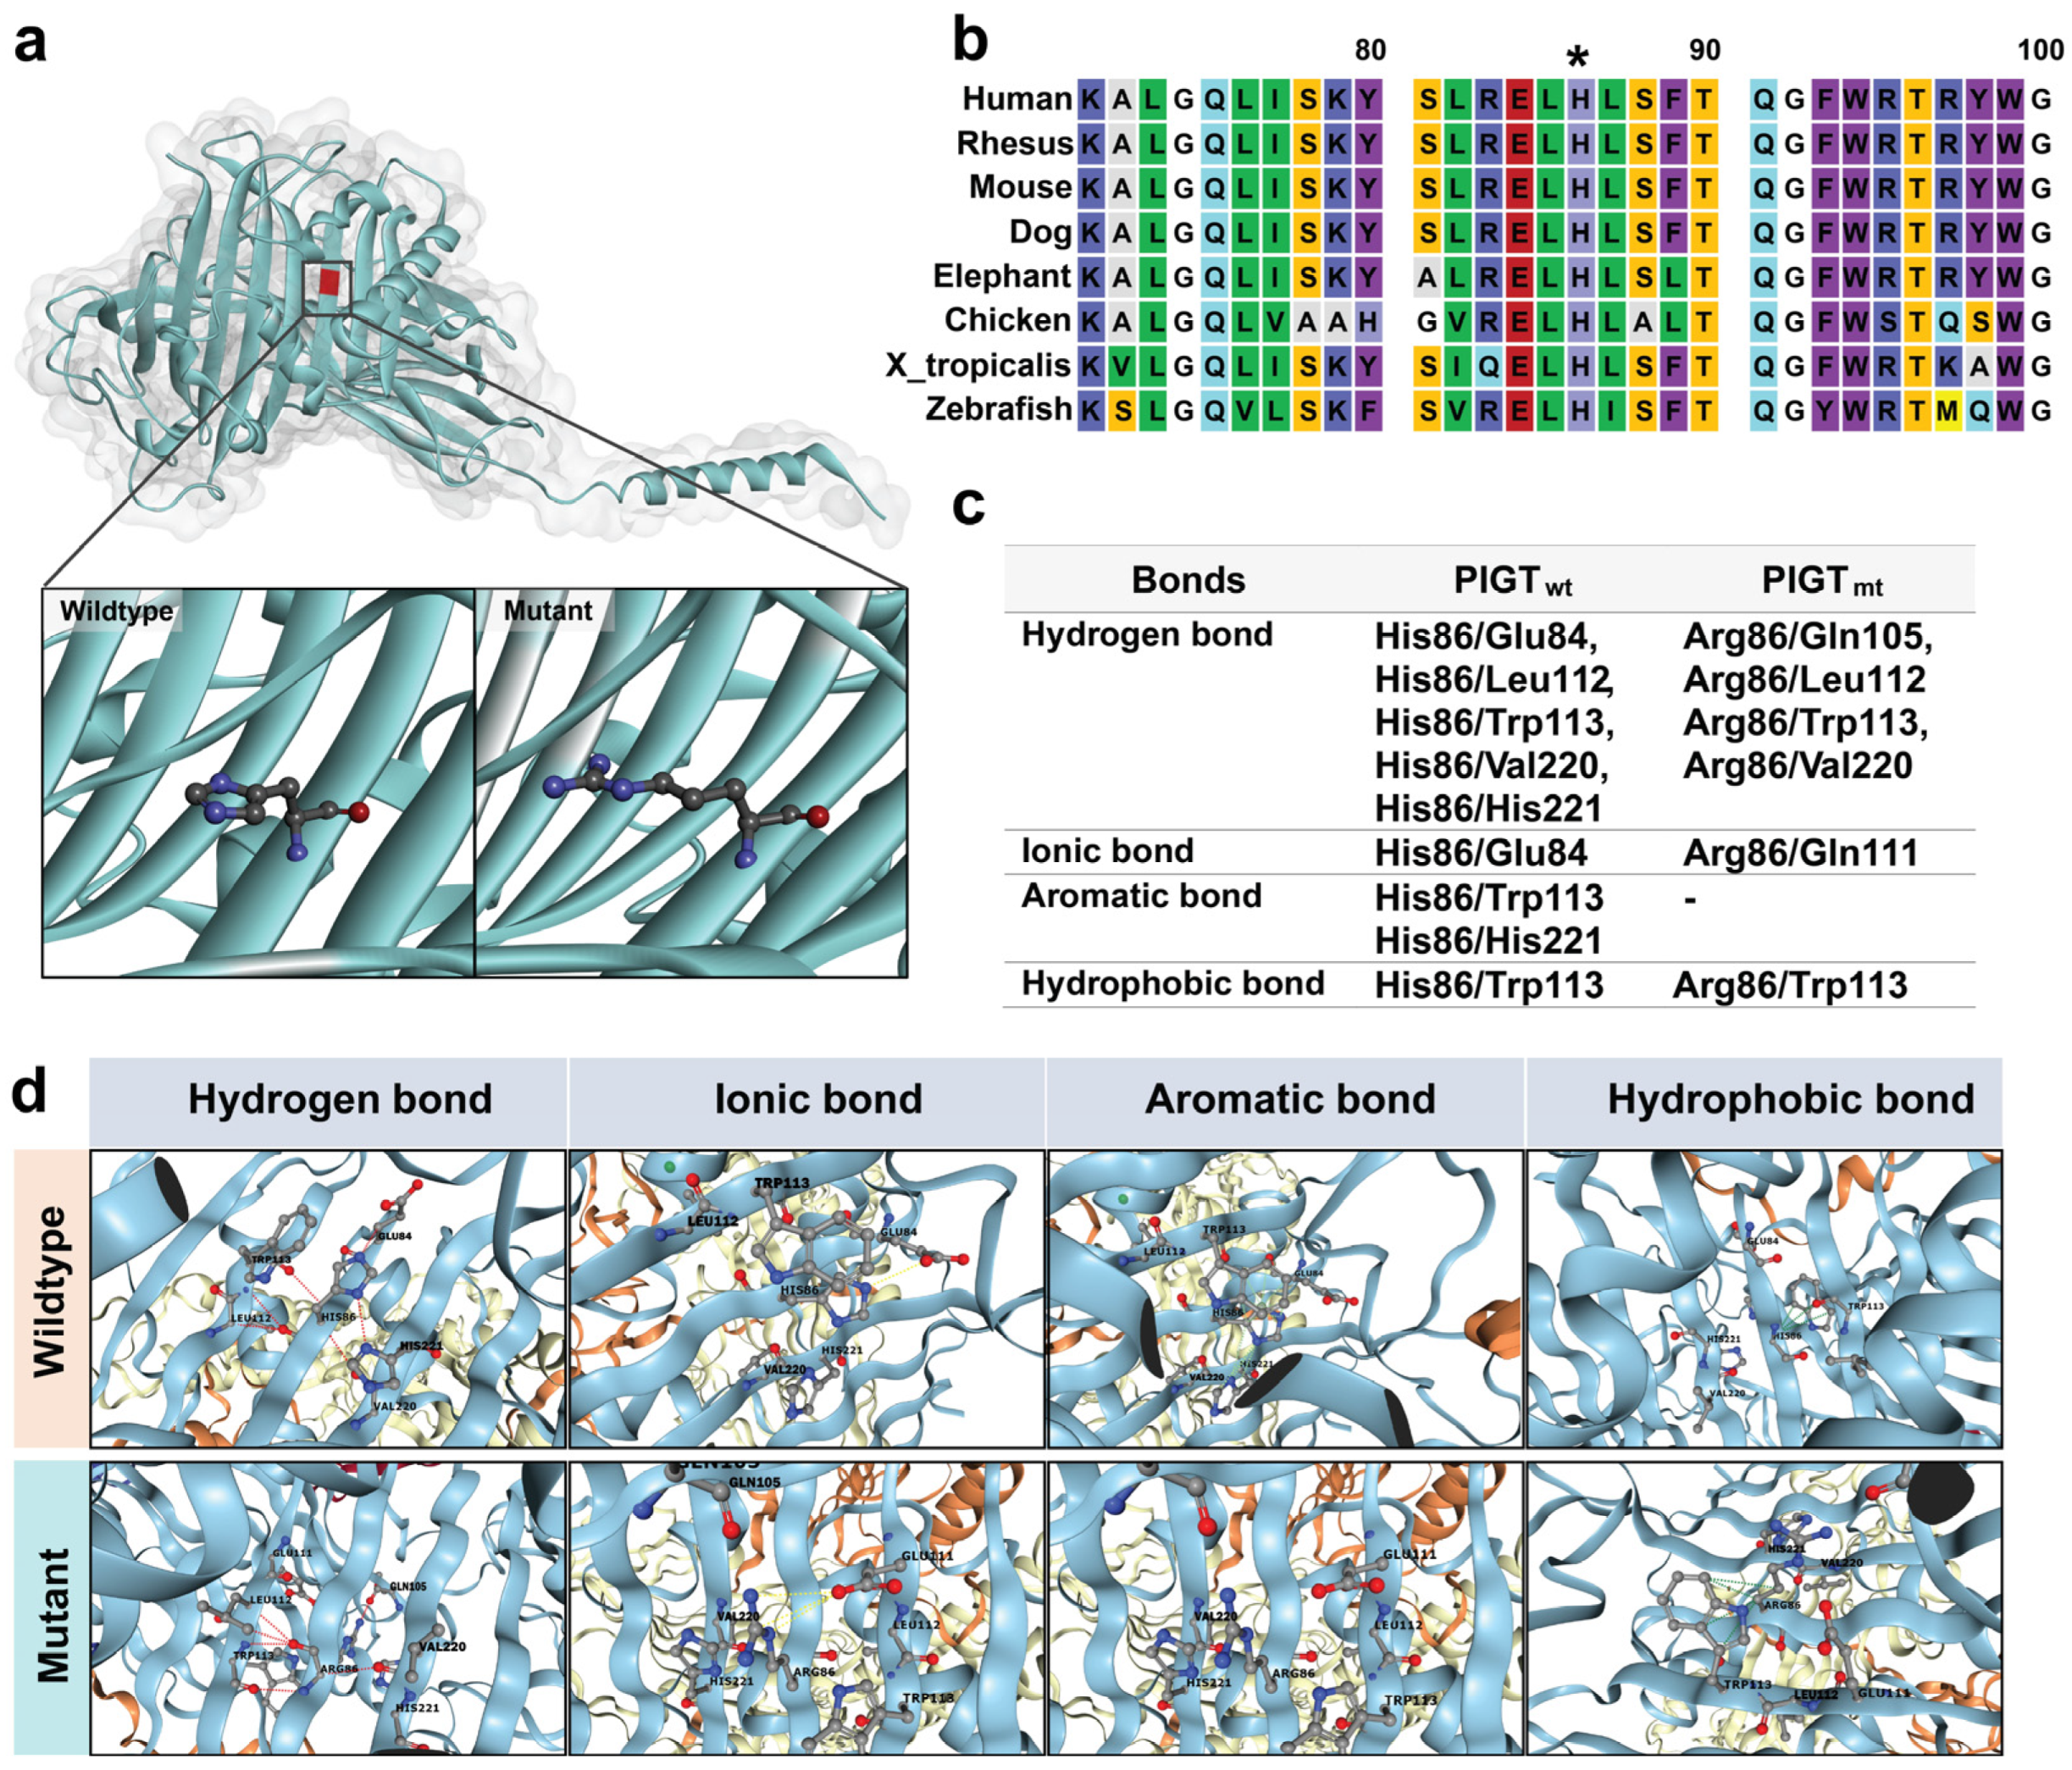

2.4. The Intramolecular Interactions Among Amino Acids at the Site of Alteration

2.5. The Prediction of Protein Stability